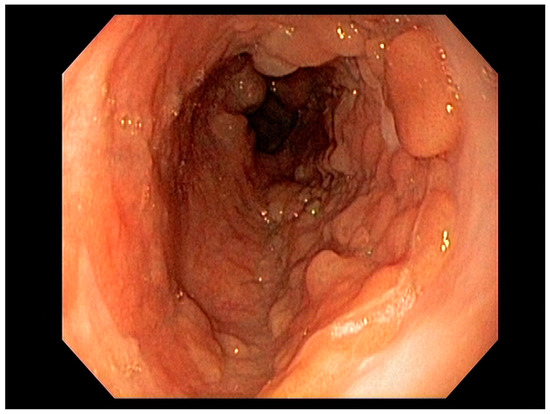

Endoscopy with high-definition white light imaging is recommended and is the standard for detecting and documenting the presence of mucosal or submucosal lesions, as shown in Figure 1. Non-invasive approaches to screening for premalignant lesions of the esophagus include devices such as the “EsophaCap” [12] and cytosponge -TFF3 that detect genetic and epigenetic alterations on samples gathered non-invasively and can be used by primary care physicians to screen for Barrett’s esophagus [13]. Non-invasive diagnostic modalities, using molecular biomarkers from a variety of body fluids to diagnose early gastric cancer, have been developed. These include “liquid-based biopsy,” which uses circulating nucleic acids. This is an exciting area of research that may change the diagnostic landscape [14].

Figure 1. Barrett’s esophagus with Nodules White Light Endoscopy.